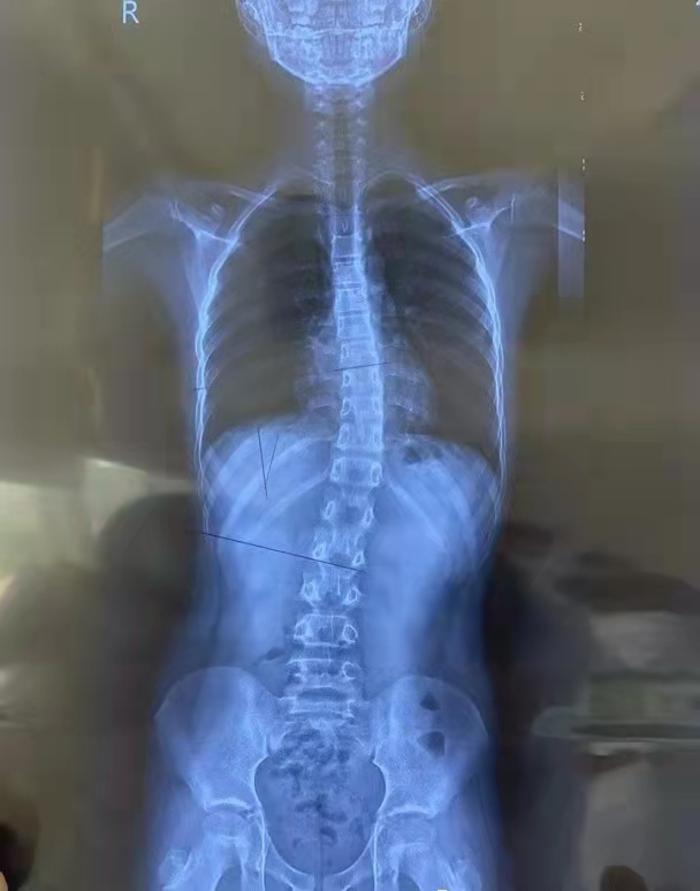

脊柱侧凸俗称脊柱侧弯,它是一种脊柱的三维畸形,包括冠状位、矢状位和轴位上的序列异常。正常人的脊柱从后面看应该是一条直线,并且躯干两侧对称。如果从正面看有双肩不等高或后面看到有后背左右不平,就应怀疑“脊柱侧弯”,这个时候应拍摄站立位的全脊柱X线片,如果正位X线片显示脊柱有大于10度的侧方弯曲,即可诊断为脊柱侧弯。

国际脊柱侧弯研究学会对脊柱侧弯的定义如下:应用Cobb法测量站立正位X线片的脊柱侧方弯曲,测量上端椎上缘延长线的垂线与下端椎下缘延长线的垂线相交所形成的角,如果此角大于10°则将其定义为脊柱侧弯。

①    Cobb角<20°者可通过运动矫正并定期随诊复查

②    Cobb角在25°~50°之间的脊柱侧弯应行矫形器治疗

③    Cobb角大于50°应采取手术治疗